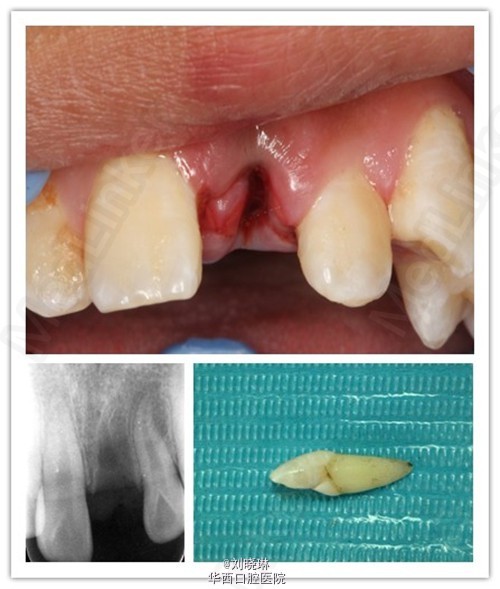

离体30小时的牙齿再植术及追踪观察

病人14岁,外伤导致上前牙脱落,患牙离体时间超过30小时。给患者讲明离体时间过长,患牙又未做正确方式保存,再植成功率低,患者要求试保留再植,术前签知情同意书。